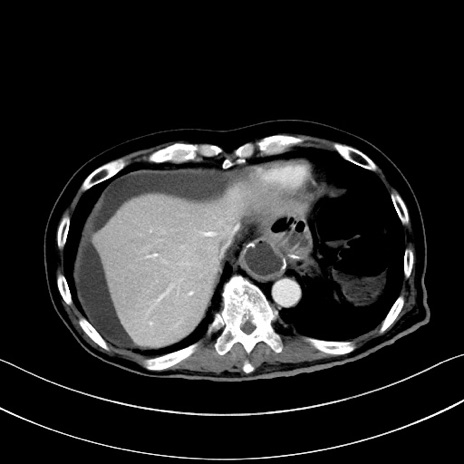

症例28(横断像)

【症例】60歳代男性

【主訴】嘔吐

【現病歴】胃癌にて胃全摘後。食思不振が悪化し、夜中に嘔吐することがある。

【既往歴】胃癌、胃全摘、脾摘、胆摘後

【データ】WBC 5900、CRP 10.56